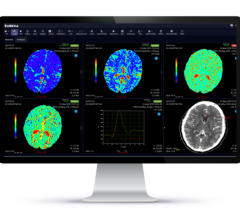

May 2, 2023 — Metabolic disorders are involved in many common health conditions such as Alzheimer's, depression ...